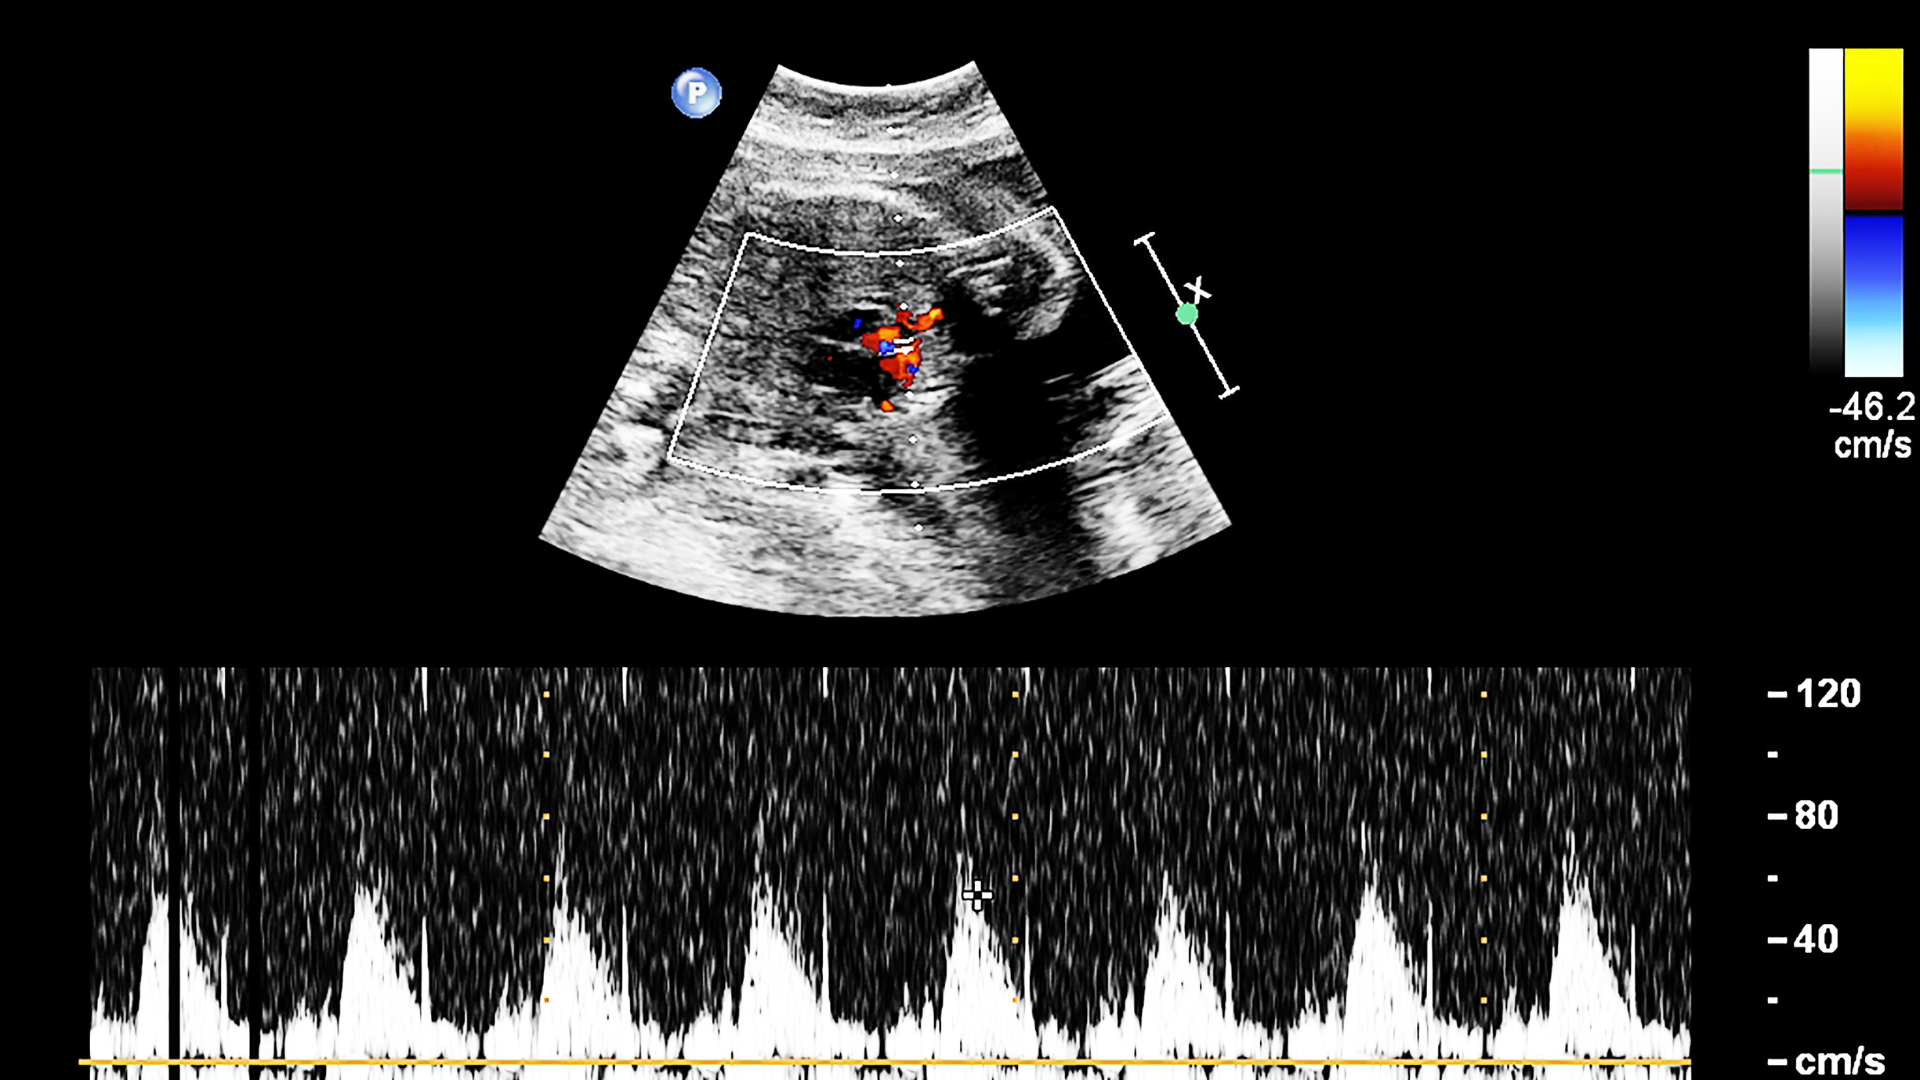

Siêu âm tim thai là phương pháp sử dụng sóng siêu âm để đánh giá cấu trúc bên trong tim của thai nhi. Khác với siêu âm thai thông thường vốn tập trung vào hình dạng và sự phát triển tổng thể, kỹ thuật này đi sâu vào hoạt động của các buồng tim, mạch máu lớn và dòng chảy của máu.

Nhờ độ chi tiết cao, bác sĩ có thể quan sát cách tim co bóp, cách các van mở và đóng và sự phối hợp giữa các mạch máu. Phương pháp này đặc biệt hữu ích khi bác sĩ cần kiểm tra những vấn đề mà siêu âm tổng quát khó phát hiện. Một số bất thường bẩm sinh liên quan đến tim có thể xuất hiện sớm, nhưng muốn nhận diện chính xác thì cần một kỹ thuật chuyên biệt như siêu âm tim.

Để kiểm tra tim thai rõ hơn, kỹ thuật này thường được thực hiện từ tuần 18 đến tuần 22 của thai kỳ. Trong khoảng thời gian này, tim thai đã phát triển đầy đủ, giúp quan sát các buồng tim, van tim và mạch máu lớn rõ ràng. Hình ảnh thu được ít bị cản trở bởi tư thế hoặc kích thước thai, do đó kết quả đánh giá cấu trúc và chức năng tim chính xác hơn.